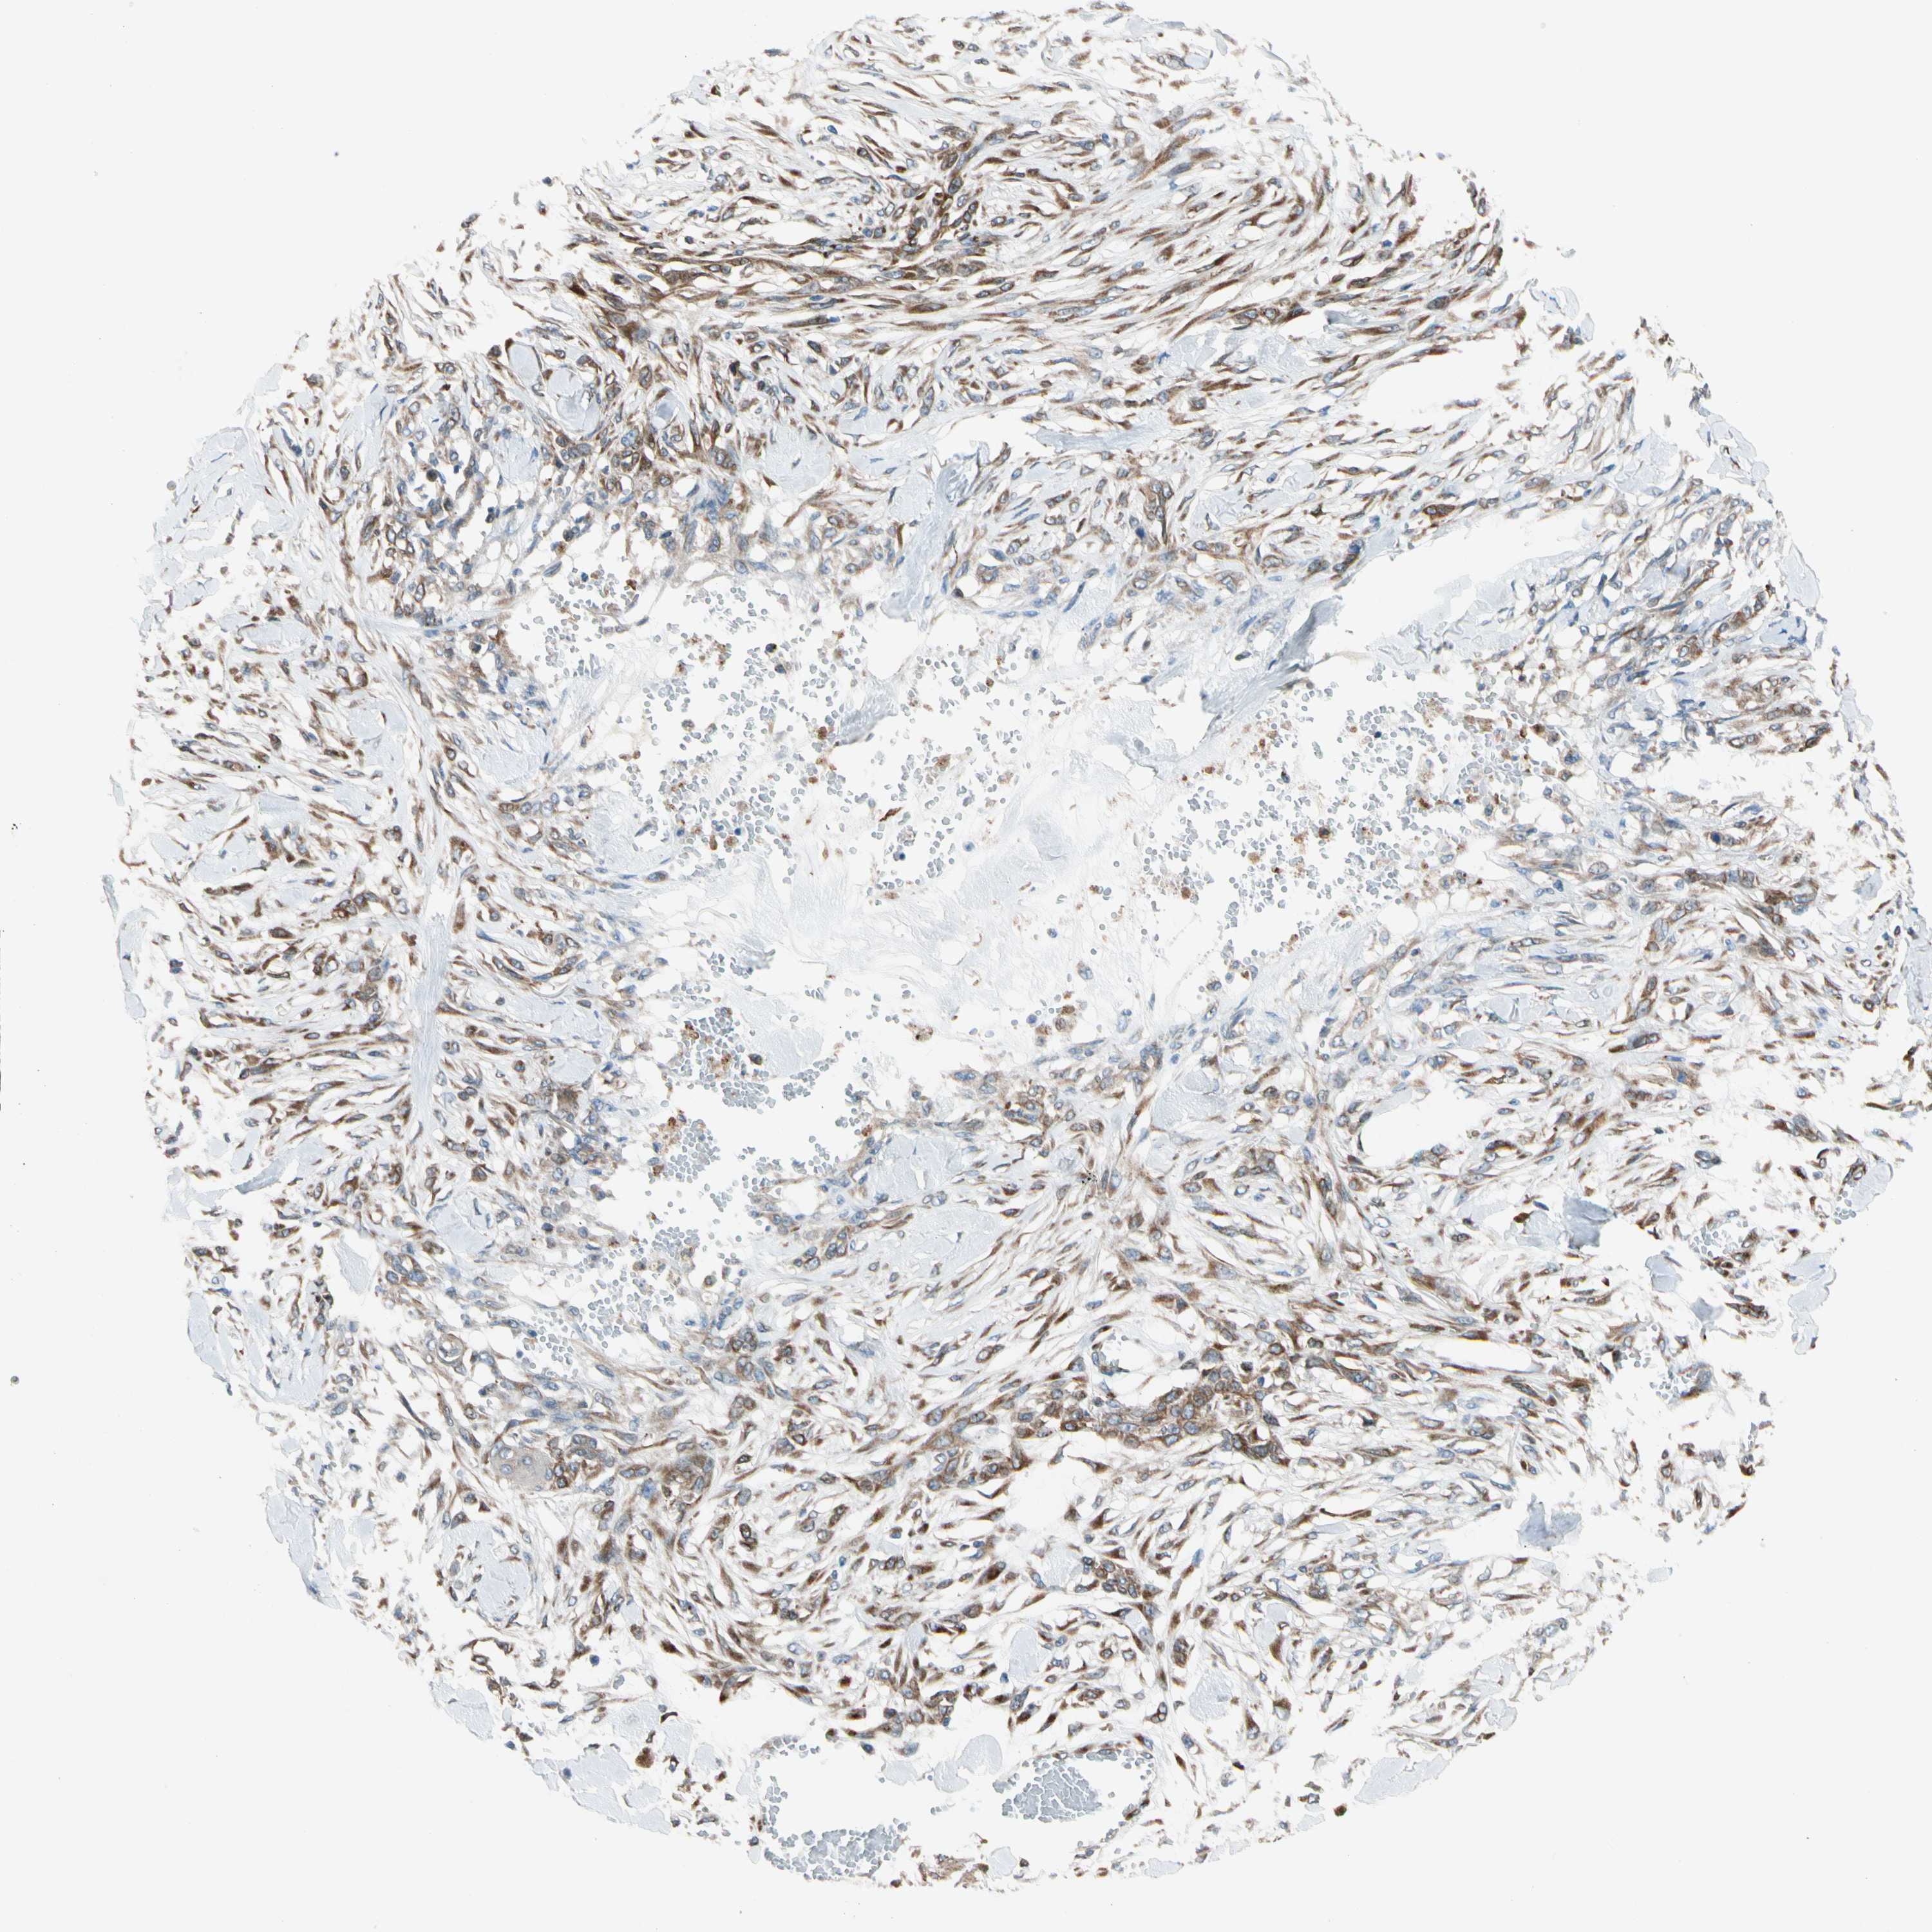

SKIN CANCER - Protein expressioni

A mouse-over function shows sample information and annotation data. Click on an image to view it in a full screen mode. Samples can be filtered based on level of antibody staining by selecting one or several of the following categories: high, medium, low and not detected. The assay and annotation is described here.

Antibody stainingi

Antibody staining in the annotated cell types in the current human tissue is reported as not detected, low, medium, or high, based on conventional immunohistochemistry profiling in selected tissues. This score is based on the combination of the staining intensity and fraction of stained cells.

Each image is clickable and will lead to virtual microscopy that enables deeper exploration of all samples and also displays staining intensity scores, fraction scores and subcellular localization as well as patient and tissue information for each sample.

Antibody HPA008176

Staining

High

Medium

Low

Not detected

Intensity

Strong

Moderate

Weak

Negative

Quantity

>75%

75%-25%

<25%

None

Location

Nuclear

Cytoplasmic/membranous

Cytoplasmic/membranous,nuclear

Squamous cell carcinoma, NOS

Basal cell carcinoma